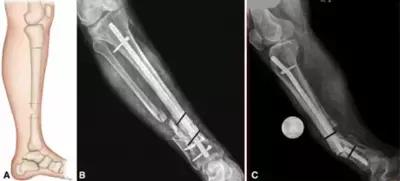

因为骨痂的生长没有感觉,所以患者最好在骨折后1个月,3个月,6个月到医院拍片检查,如果出现骨痂没有生长,骨折线清晰的状况,要连续两个月,每月检查。连续3个月骨痂没有生长,就是有骨不愈合的倾向,要及时治疗。

骨不愈合(骨不连)治疗并不难,难得是骨组织及周围生理环境的改善和性能提升上,建议中医保守靶位体液渗透疗法治疗骨不连,中西医结合的治疗方法,外敷患部促进骨的生长,想了解更多,还有其他关于骨不连治疗的相关问题,私信我们吧!